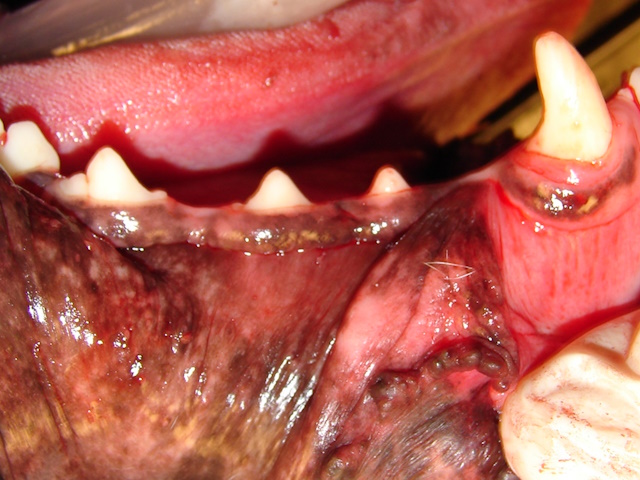

In this Dachshund breed dog, due to significant periodontal disease and bone loss, both left and right upper canines fell off, leaving openings in the mouth that communicate with the nasal cavity (oronasal fistulas).

Both oronasal fistulas were surgically corrected using single-layer buccal mucoperiosteal advancement flaps.